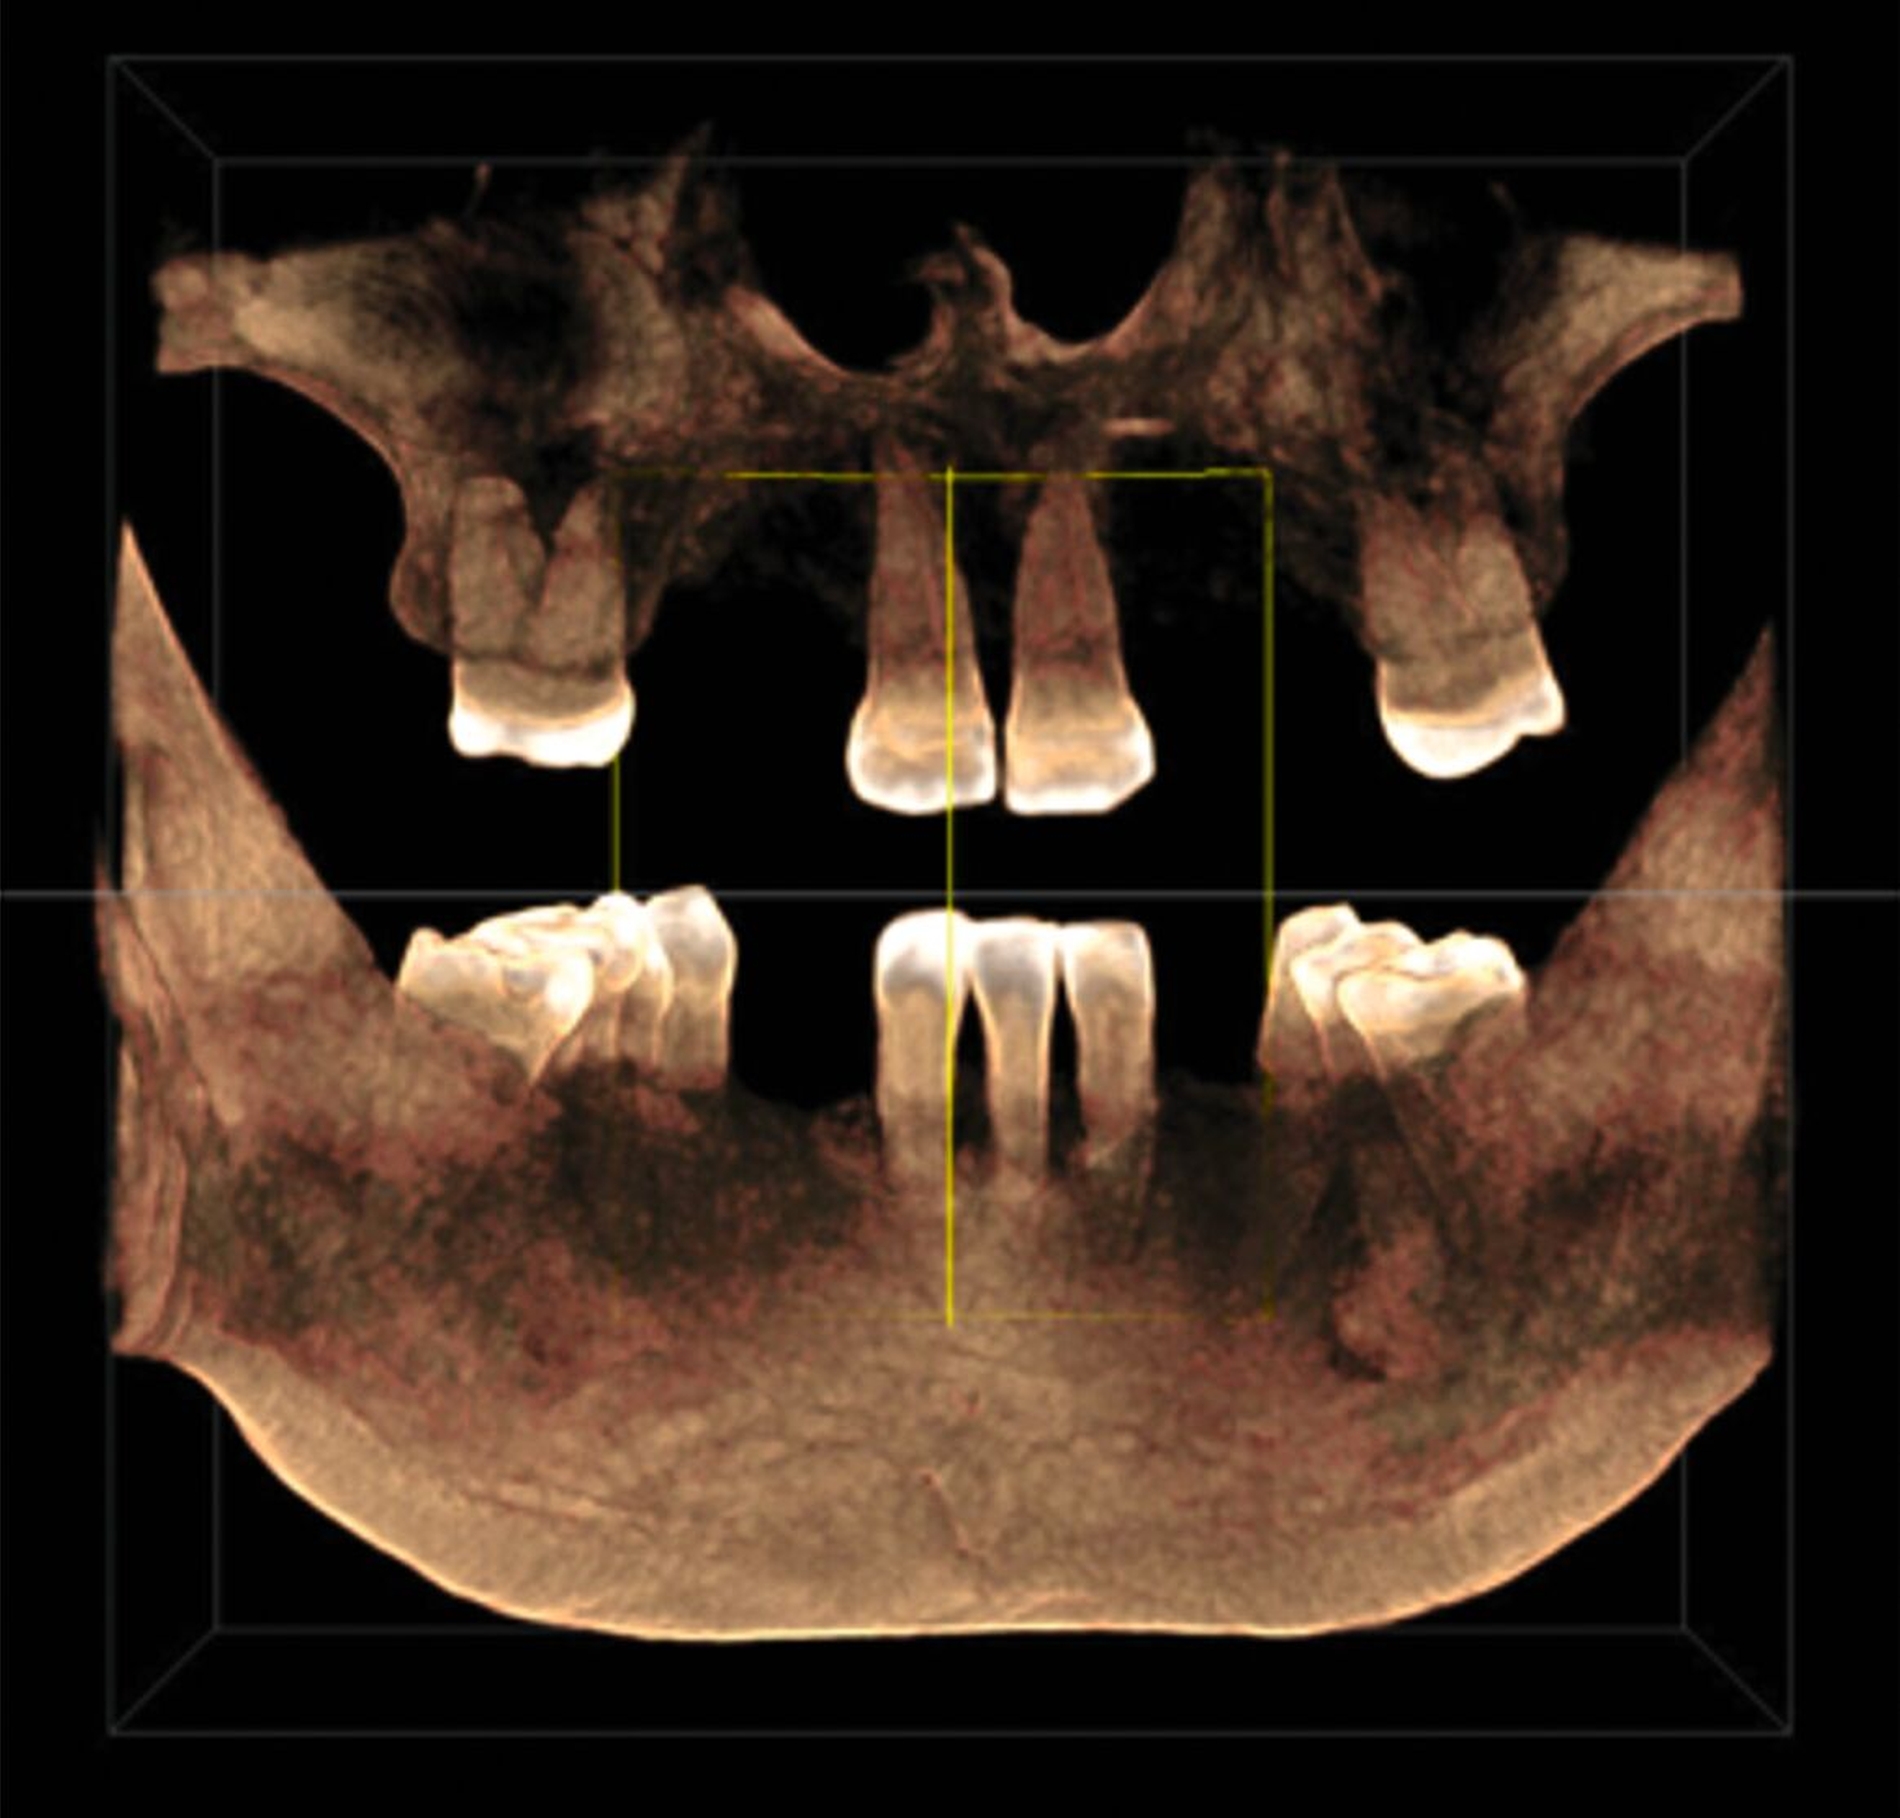

Zur Implantationsplanung wurden nach Abschluss der Vorbehandlungen und Prophylaxemaßnahmen zunächst eine digitale Volumentomografie (DVT) sowie aktuelle Situationsmodelle von Ober- und Unterkiefer zur Beurteilung der ossären Ausgangssituation erstellt. Es folgte die digitale Planung der Implantationen an den Regionen 12, 13, 13, 22, 23, 25, 33 und 43 (CoDiagnostiX Dental Wings, Straumann, Basel, Schweiz) sowie die Übertragung der dreidimensional geplanten Implantationen in gedruckte Bohrschablonen und die Festlegung von Art und Zeitpunkt erforderlicher Augmentationen (Abbildung 5).